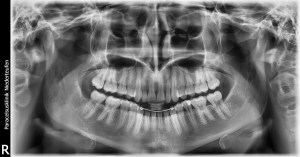

Upon arriving at the Klinik, I first had a panoramic X-ray of my jaw taken at the Paracelsus Dental Office. They are very concerned here with any type of toxic metal that might have been glued to my teeth, via fillings or oral surgery. Last spring I had my four impacted wisdom teeth removed surgically at CHOP by a wonderful doctor from the Hospital at the University of Penn (HUP). I, also, had a bilateral tonsillectomy preformed at Lankenau Hospital in the beginning of this past summer. The ENT reported after the surgery that he was ultimately thankful he had agreed to do the operation on a somewhat “high-risk” patient, because of how deeply and chronically infected my tonsils looked once removed. He admitted there was far more extensive damage from repeated insults of bacterial disease than he possibly could have seen without having gone in surgically.